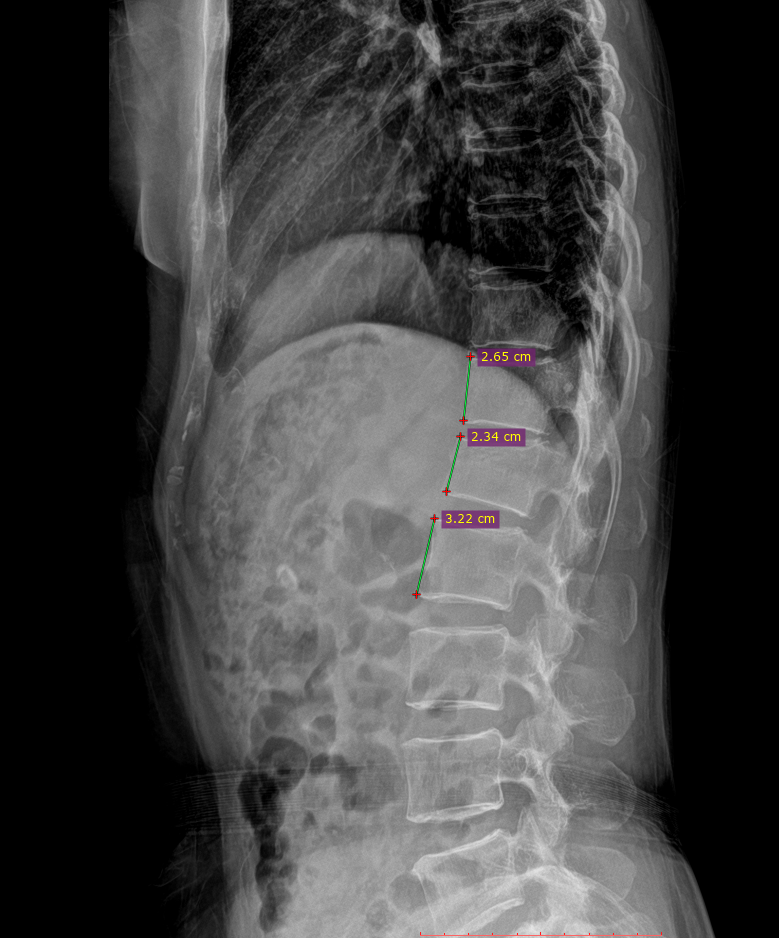

이 사건의 의뢰인은 상대방이 동석한 교통사고 피해자로서 사고 후 요통으로 ○○병원 응급실에 내원하였고 “제2요추폐쇄증후군” 진단을 받았다. 방사선 검사에서 “압박 골절”이 나타났습니다. 부상 초기에 척추의 추가 기형이 진행되거나 신경학적 증상이 나타나면 수술을 준비하고 며칠 동안 경과를 지켜보십시오. 다행스럽게도 통증은 신경학적 증상 없이 차차 가라앉았고, 정형외과를 통한 보존적 치료만이 상당 기간 지속되다가 치료가 종료되었다.

응급실 기록